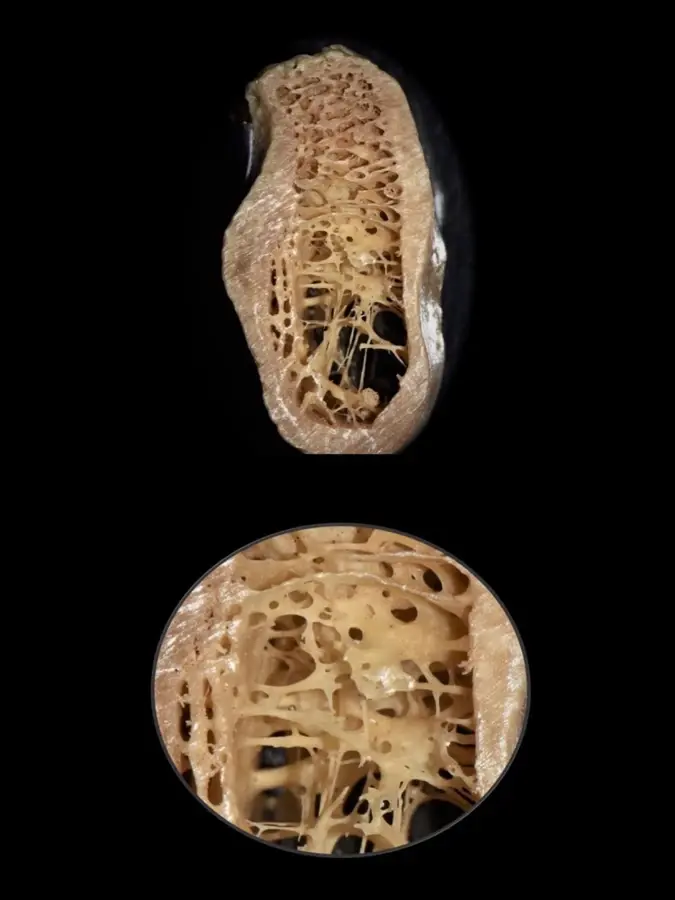

Durante años, se establecieron las propiedades biomecánicas del hueso basándose únicamente en medidas a gran escala, pudiendo diferenciarse entre el hueso trabecular y el hueso cortical. Sin embargo, actualmente es posible un mayor análisis a nivel micrométrico que permite explorar entre los componentes orgánicos, tisulares, celular y moleculares. Es así que gracias a aproximaciones nanoestructurales se muestran asociaciones entre las propiedades biomecánicas y las calidades óseas, las que se pueden presentar tanto en el hueso cortical como en el trabecular de manera indistinta. En el cortical, el espacio poroso ocupa el 5-10%, mientras que en el trabecular se encuentra en el 30-90% del total de la estructura9 (Figura 1).

Figura 1. Sector postero-inferior de la mandíbula donde se aprecia una cortical gruesa y hueso esponjoso con espacios medulares amplios (arriba) y trabéculas bastante finas (debajo), muchas veces del espesor de un cabello (0,025 mm).

Por ejemplo, se dice que el sector anteroinferior de la mandíbula suele presentarse hueso tipo I y en el posteroinferior tipo II. La variante en la zona posterioinferior mandibular se debe a que, a pesar de tener una buena cortical ósea y cantidad de hueso esponjoso, la dimensión de los espacios medulares es muy amplia y el grosor de las trabéculas tan finas como el espesor de un cabello11 (Figura 3).